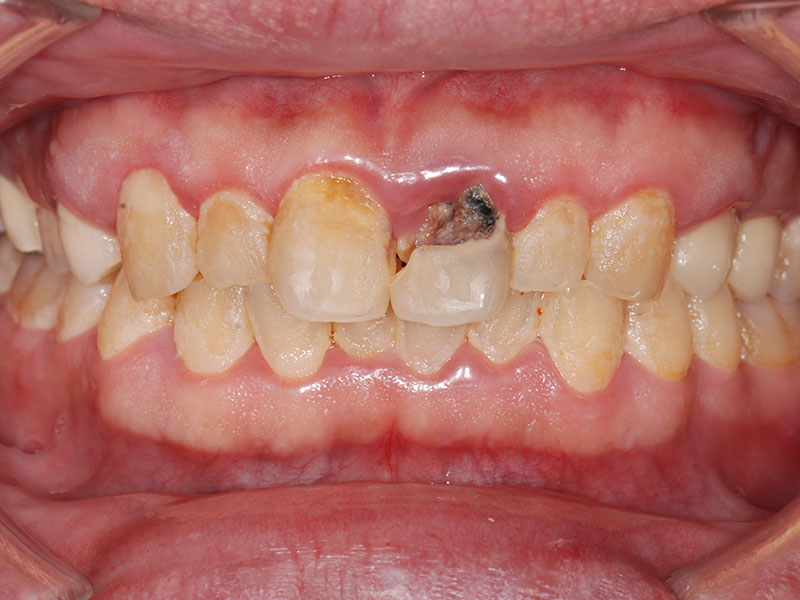

治療前